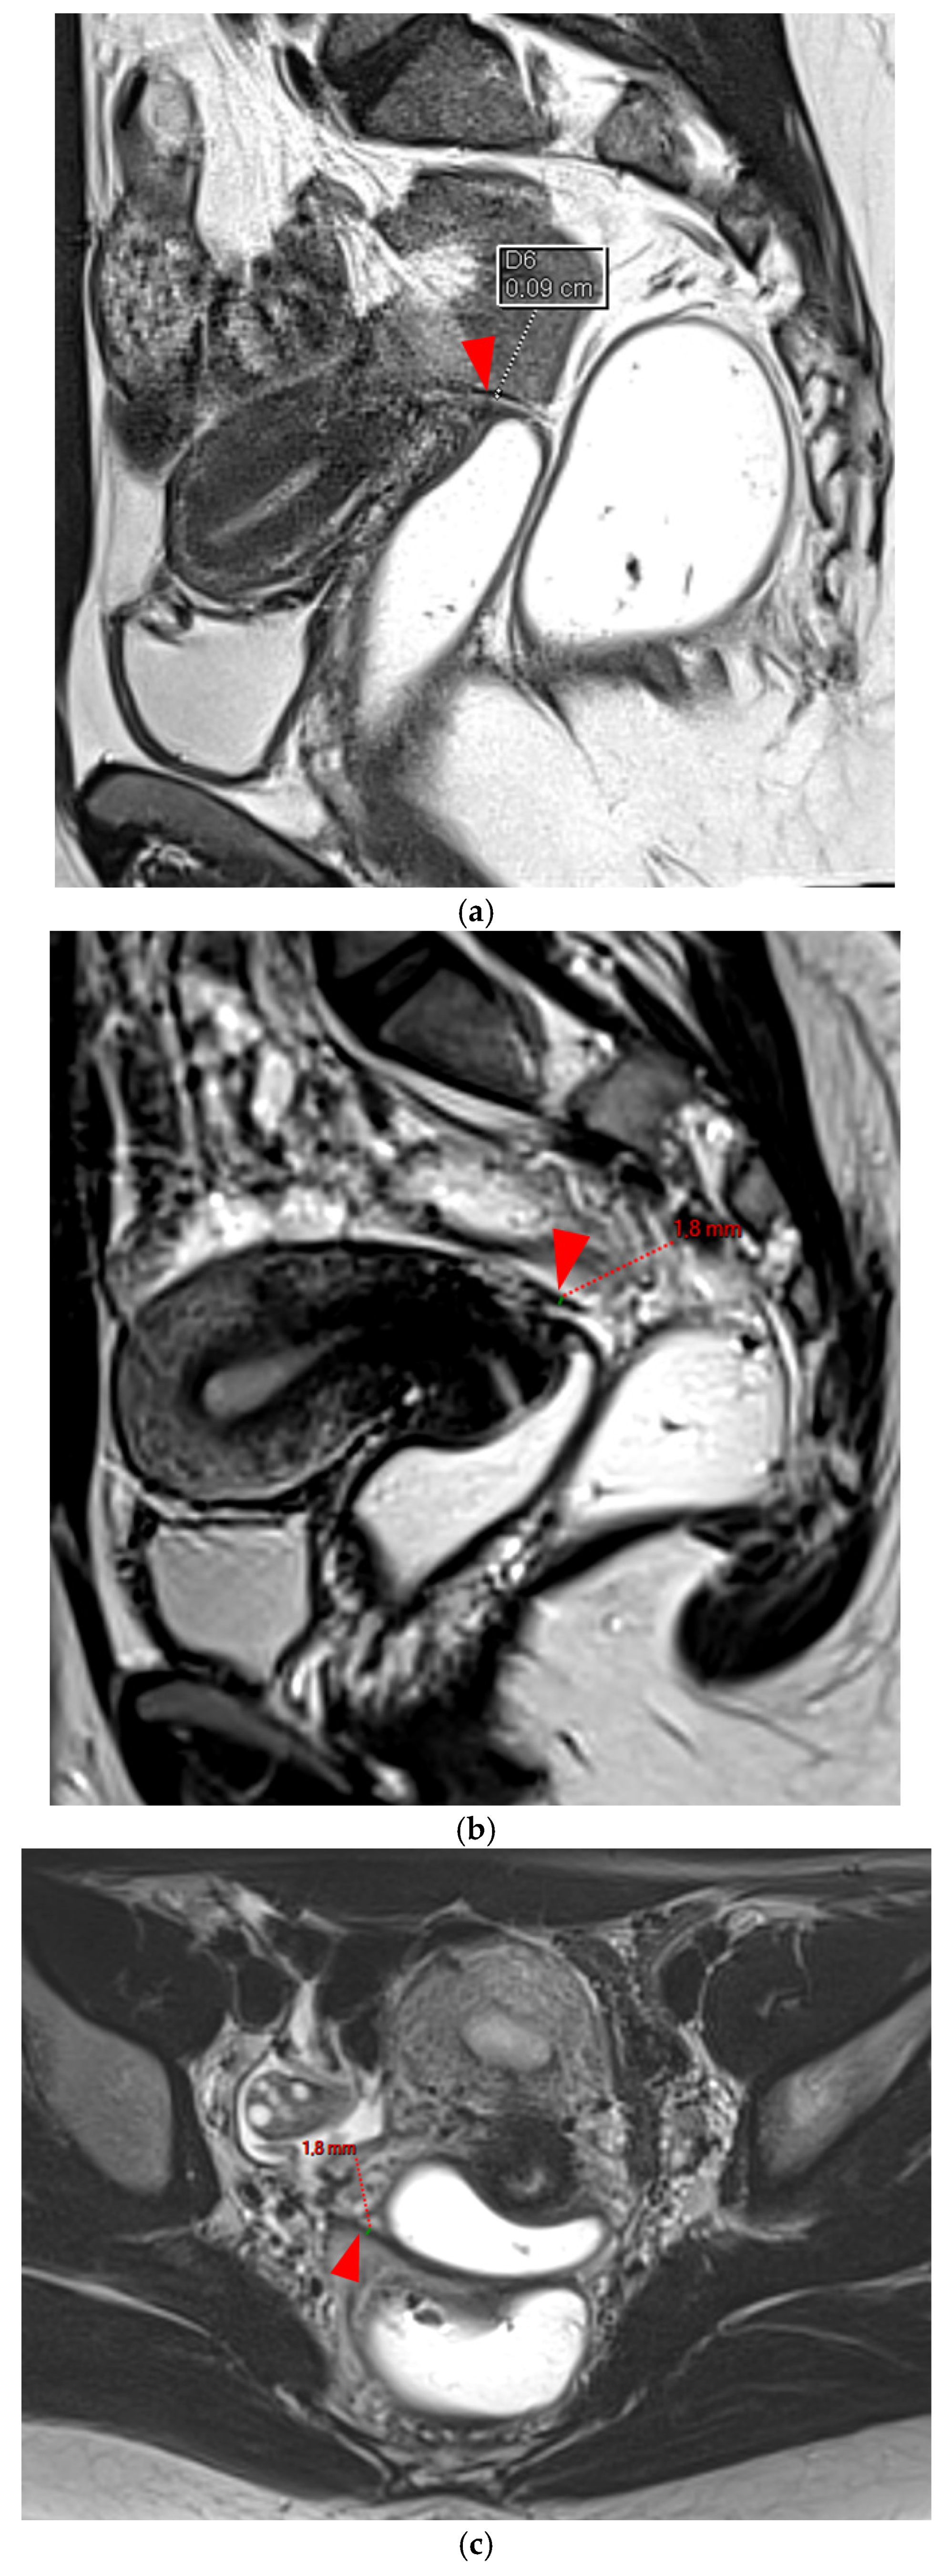

Diagnostics 15 01508 g001

Figure 2. Pelvic MRI scans of five patients with visible but thin (≤2 mm), smooth, and regular USLs (HTD type 2). (a) Sagittal T2WI: right USL (arrowhead). (b) Sagittal T2WI: right USL (arrowhead). (c) Axial T2WI: right USL (arrowhead). (d) Axial T2WI: left and right USLs (arrowheads). (e) Axial T2WI: right USL (arrowhead).

A type 2 USL (Figure 2) is visible on MRI scans as a curvilinear T2 hypointense structure that mainly originates from the posterior uterine wall at the uterocervical junction, where the torus uterinus is located, and courses dorsocranially toward the sacrum. A type 2 USL is either visible but not measurable due to its minimal thickness (i.e., ≤1 mm), or visible and measurable but thin (i.e., between 1 mm and 2 mm, inclusive of 2 mm). It appears smooth with regular margins and often displays a longitudinally tapering shape.